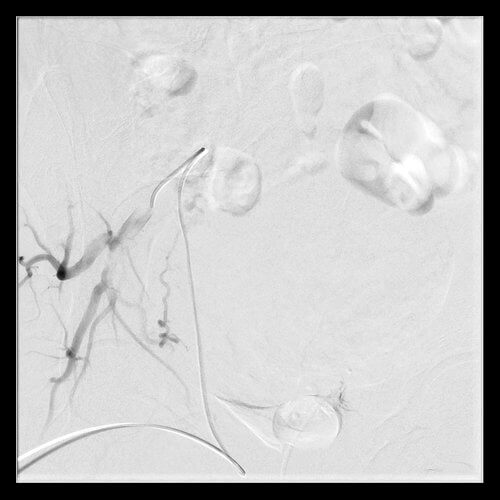

42 year old female who presents with abnormal bleeding, menstrual cramping, and frequent urination and subsequently undergoes UFE.

42 year old female who presents with abnormal bleeding, menstrual cramping, and frequent urination and subsequently undergoes UFE.